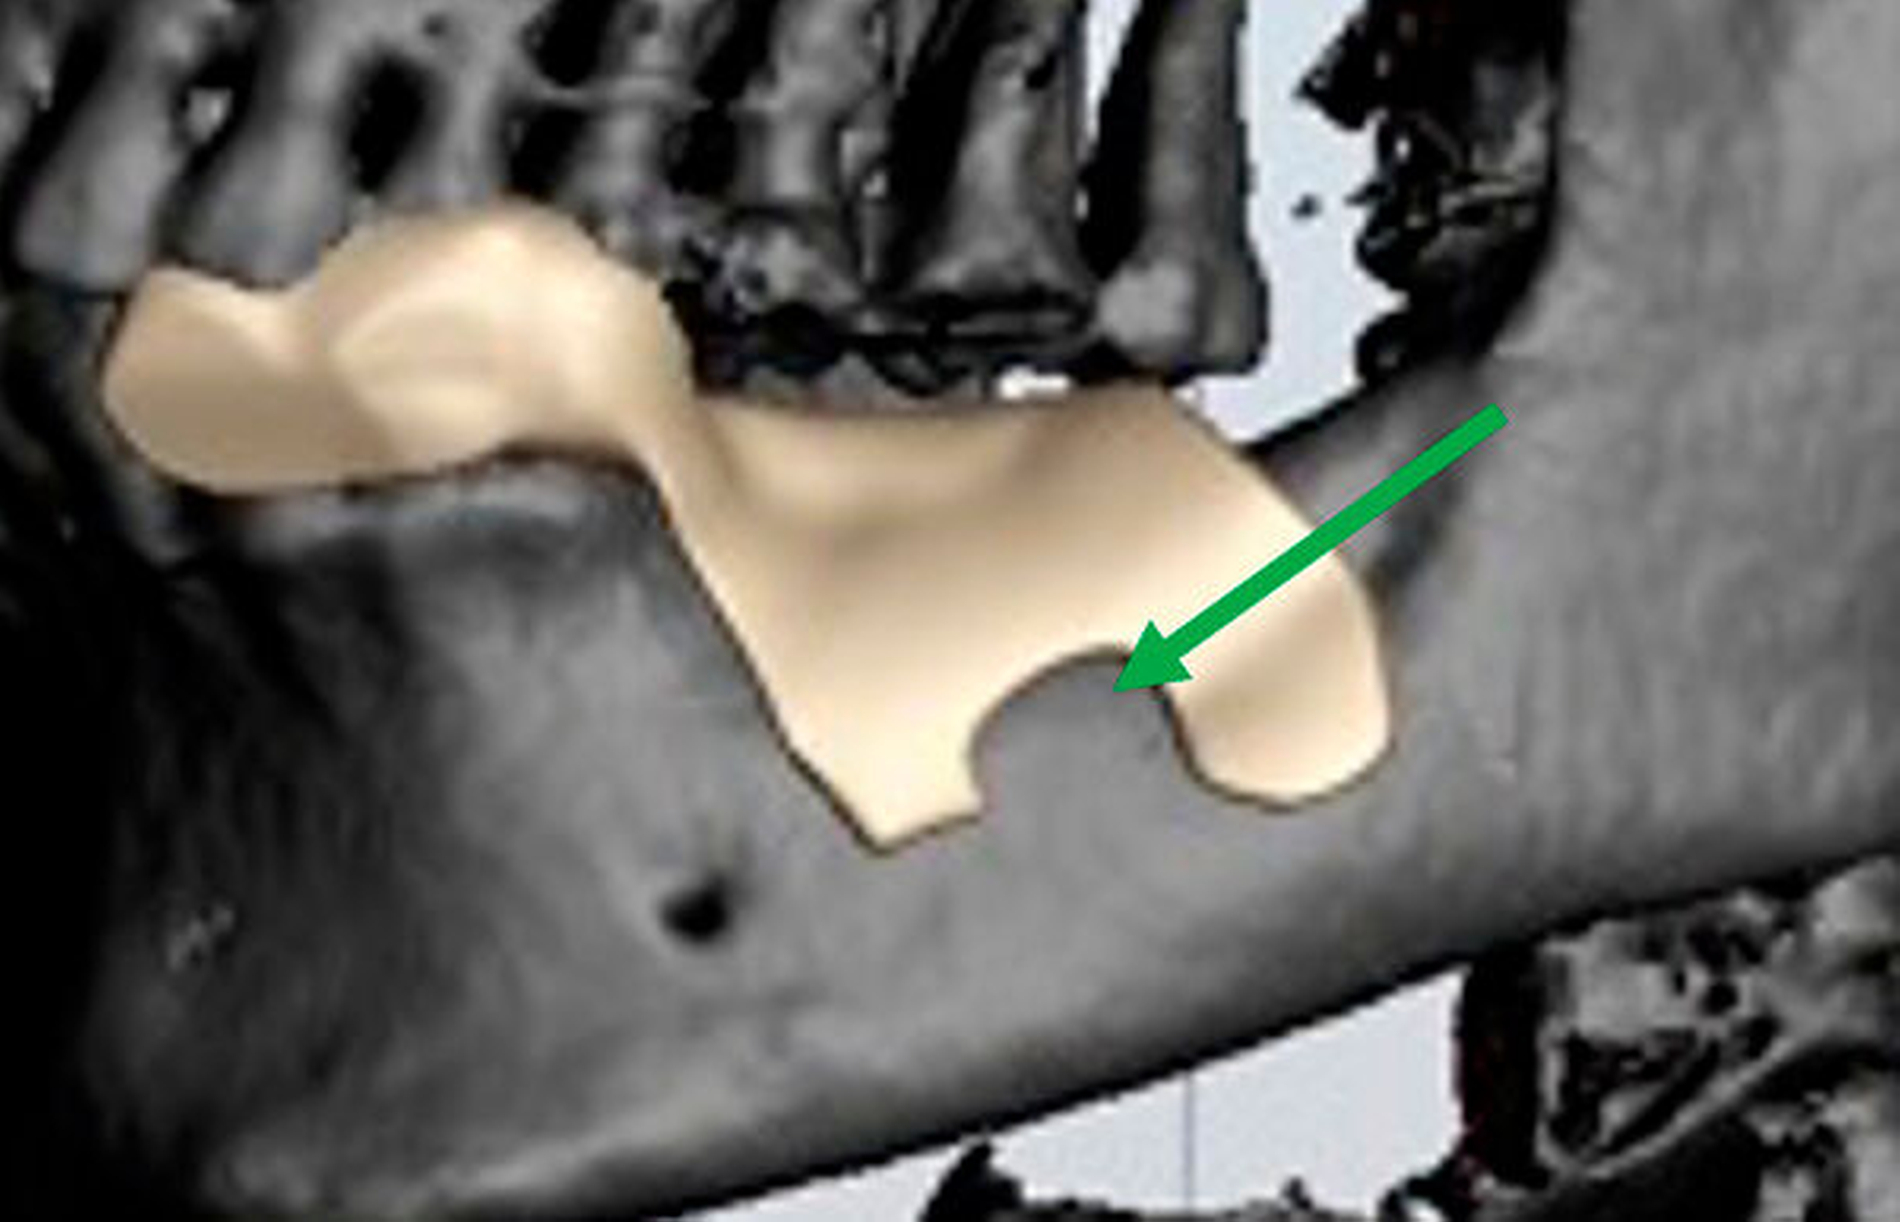

Aufgrund der tiefen intraossären Lage ohne direkten Zahnbezug oder andere klare Orientierungspunkte wurde zur gezielten Ansteuerung auf Basis des DVT-Datensatzes eine Osteotomie-Schablone 3-D-gedruckt (Material: MED 610, Drucker: EDEN 260V, Stratasys), die den Osteotomiezugang genau verschlüsselte (Abbildung 3a). Intraoperativ konnte dadurch die Keratozyste gezielt entfernt werden, ohne dass eine großflächige Osteotomie notwendig war oder ein erhöhtes Risiko für die Verletzung des N. alveolaris inferior bestand (Abbildung 3b). Der Befund wurde zystekotomiert und die Knochenhöhle zusätzlich ausgefräst (Abbildung 4). Auch die postoperative radiologische Kontrolle bestätigte eine optimale Lage der Osteotomie (Abbildung 5). Die postoperative Heilung war unproblematisch, drei Jahre nach dem Eingriff ist die Patientin rezidivfrei (Abbildung 6).

Im vorliegenden Fall wäre aufgrund der tief intraossären Lage ohne Osteotomie-Schablone auf jeden Fall eine großflächige Osteotomie notwendig gewesen, um die Rezidiv-Keratozyste aufzufinden. Zusätzlich zum damit einhergehenden Verlust an Knochenhartsubstanz besteht bei einer solchen explorierenden Osteotomie des lateralen Unterkiefers ein größeres Risiko einer Nervverletzung. Um dies zu vermeiden, verschlüsselt die 3-D-gedruckte Schablone sicher die Position einer nervfernen Osteotomie, was die Gefahr für eine Schädigung des Nervens reduziert. Mit einer chirurgischen Schablone kann eine erhöhte Sicherheit für den Operateur und den Patienten erzielt werden [Nickenig et al., 2012].

Die Basis für eine schablonengestützte Chirurgie ist ein dreidimensionaler Röntgendatensatz, der in eine 3-D-Datei, zum Beispiel im „.stl“-Format (standard tesslation language), überführt wird, und an dem dann die virtuelle Operation simuliert werden kann [Goetze et al., 2017; Goetze et al., 2020]. Nach virtuellem Festlegen der gewünschten Osteotomie wird diese dann über eine computerassistiert gestaltete digitale Schablone verschlüsselt. Dies nutzt die patienteneigene Anatomie zur optimalen Ausformung der Positionierung als Modell. Der Datensatz wird exportiert und mit einem biokompatiblen Material, zum Beispiel mittels 3-D-Druck, gefertigt. Die daraus entstandene Schablone kann dann nach entsprechender Desinfektion beziehungsweise Sterilisation im Patienten angewandt werden [Goetze et al., 2017].